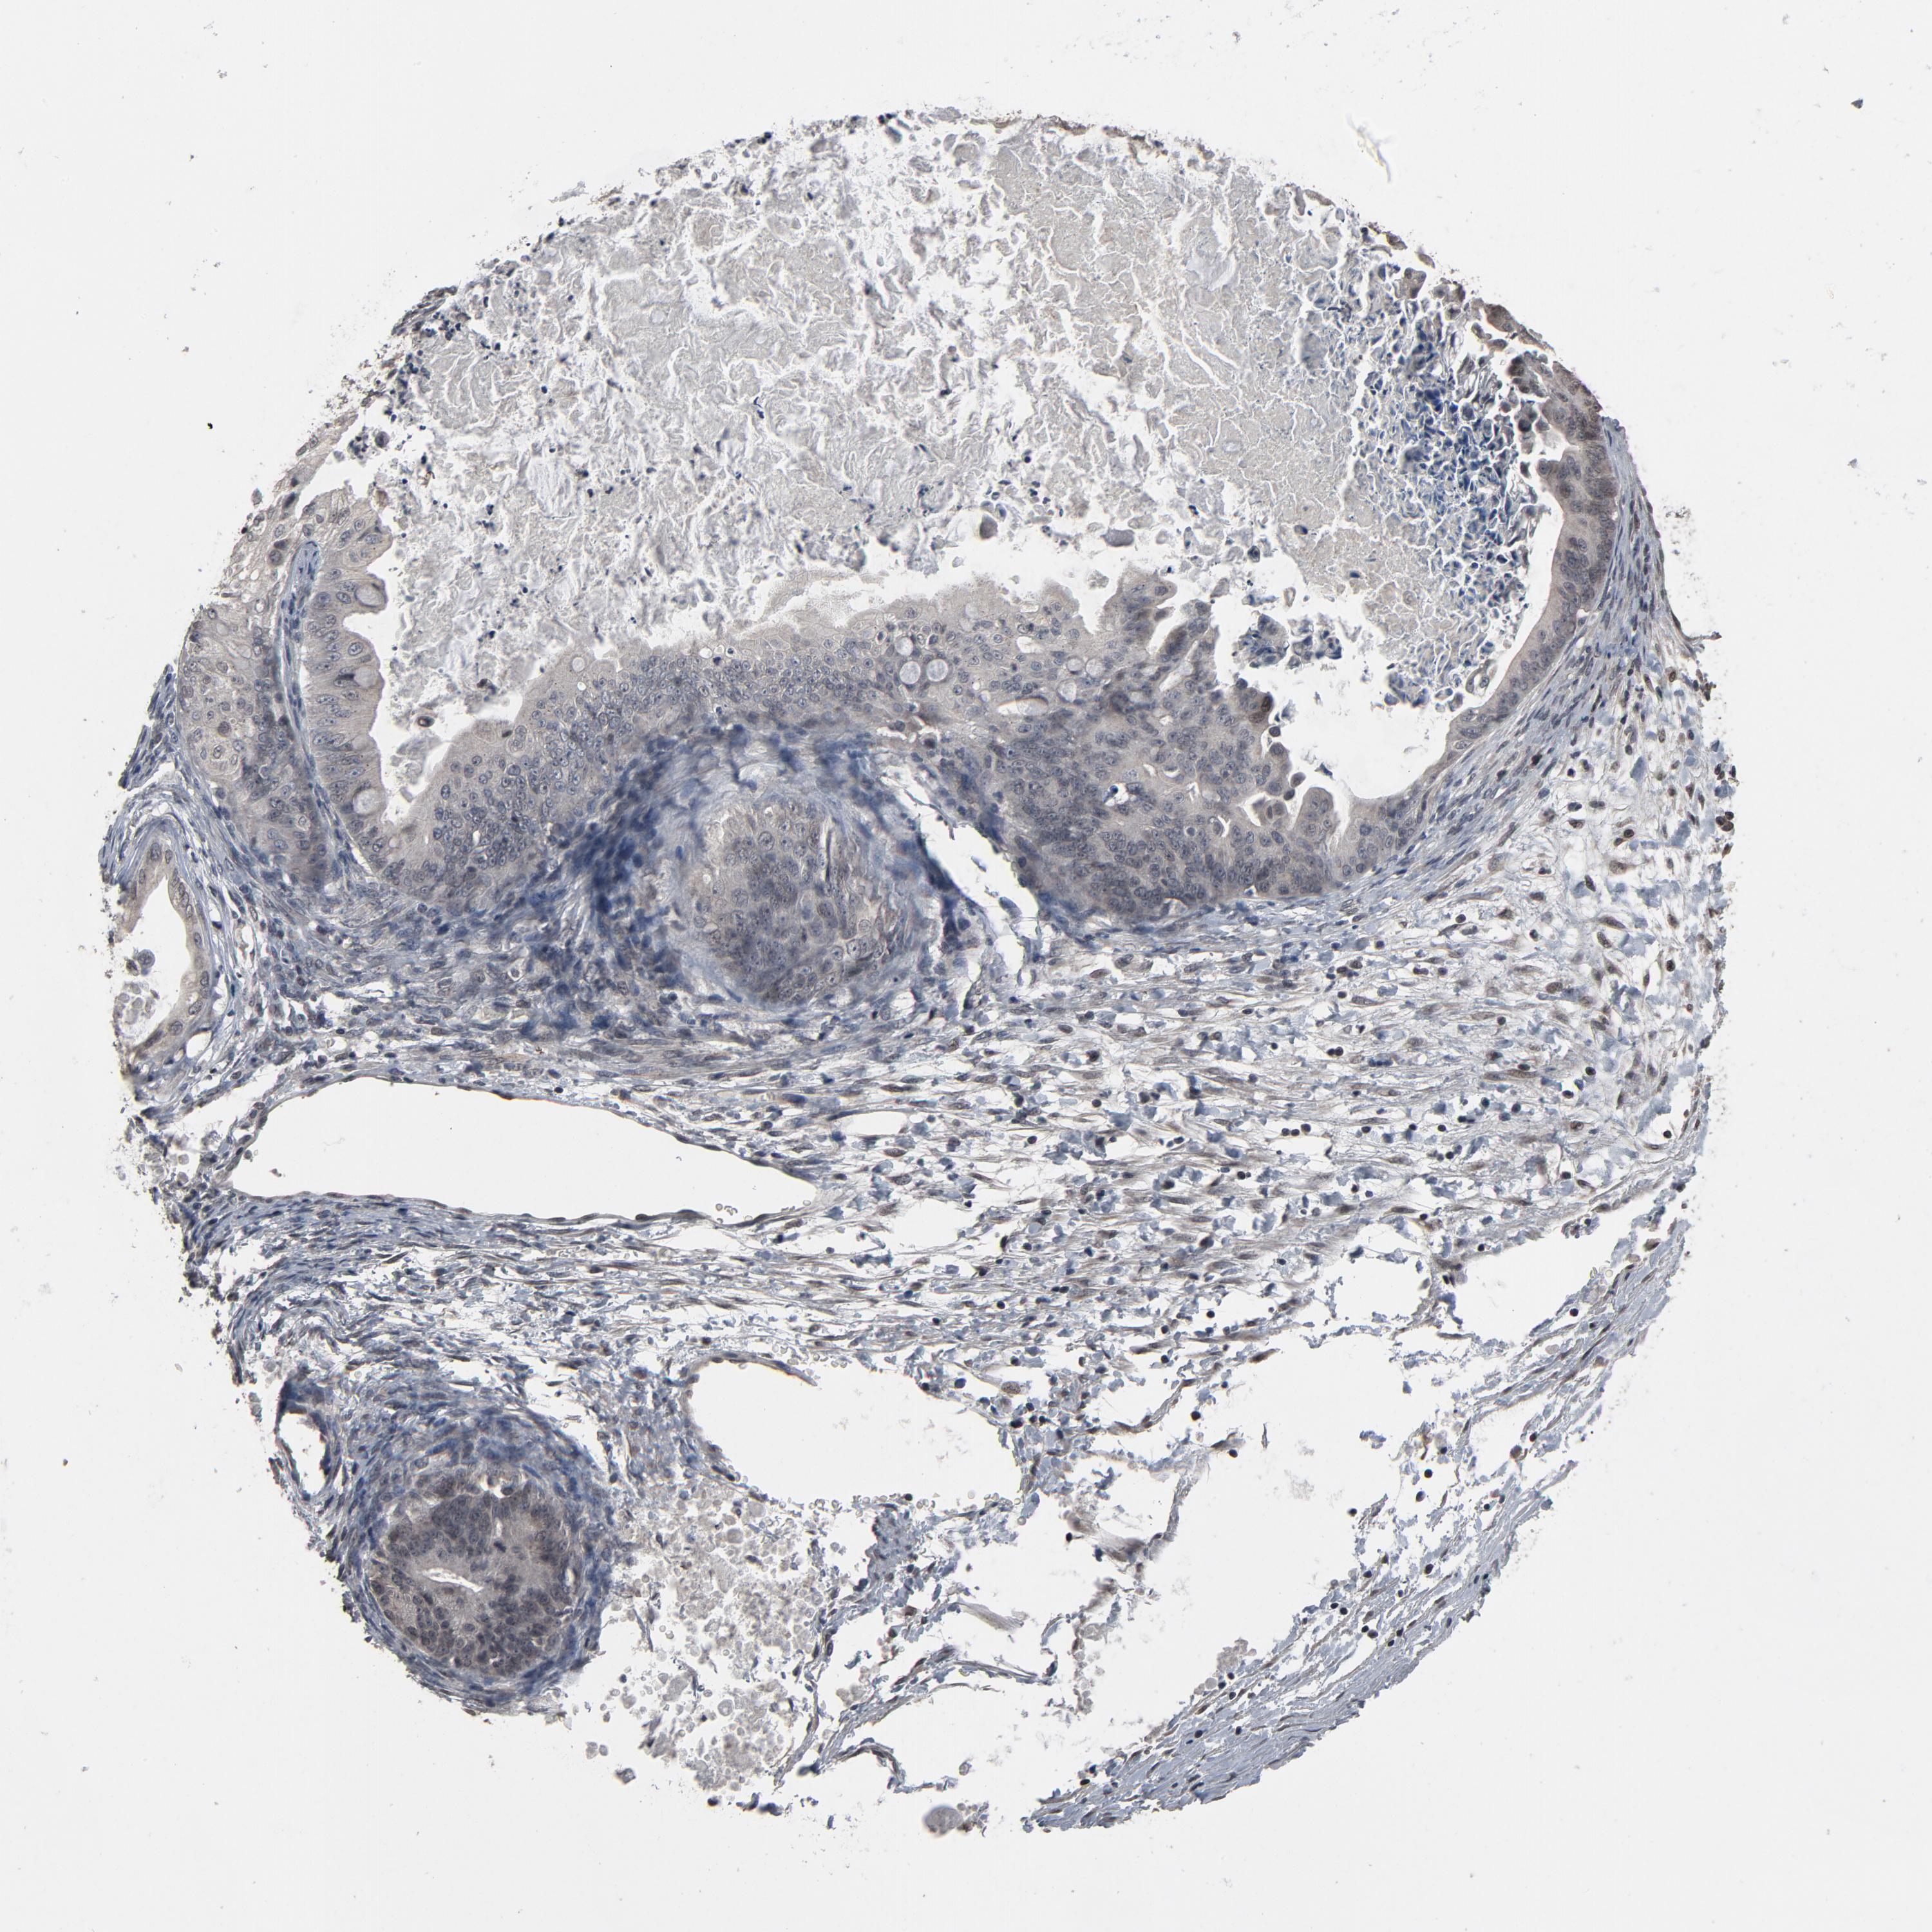

OVARIAN CANCER - Protein expressioni

A mouse-over function shows sample information and annotation data. Click on an image to view it in a full screen mode. Samples can be filtered based on level of antibody staining by selecting one or several of the following categories: high, medium, low and not detected. The assay and annotation is described here.

Note that samples used for immunohistochemistry by the Human Protein Atlas do not correspond to samples in the TCGA dataset.

Antibody stainingi

Antibody staining in the annotated cell types in the current human tissue is reported as not detected, low, medium, or high, based on conventional immunohistochemistry profiling in selected tissues. This score is based on the combination of the staining intensity and fraction of stained cells.

Each image is clickable and will lead to virtual microscopy that enables deeper exploration of all samples and also displays staining intensity scores, fraction scores and subcellular localization as well as patient and tissue information for each sample.

Antibody HPA043809

Cystadenocarcinoma, serous, NOS